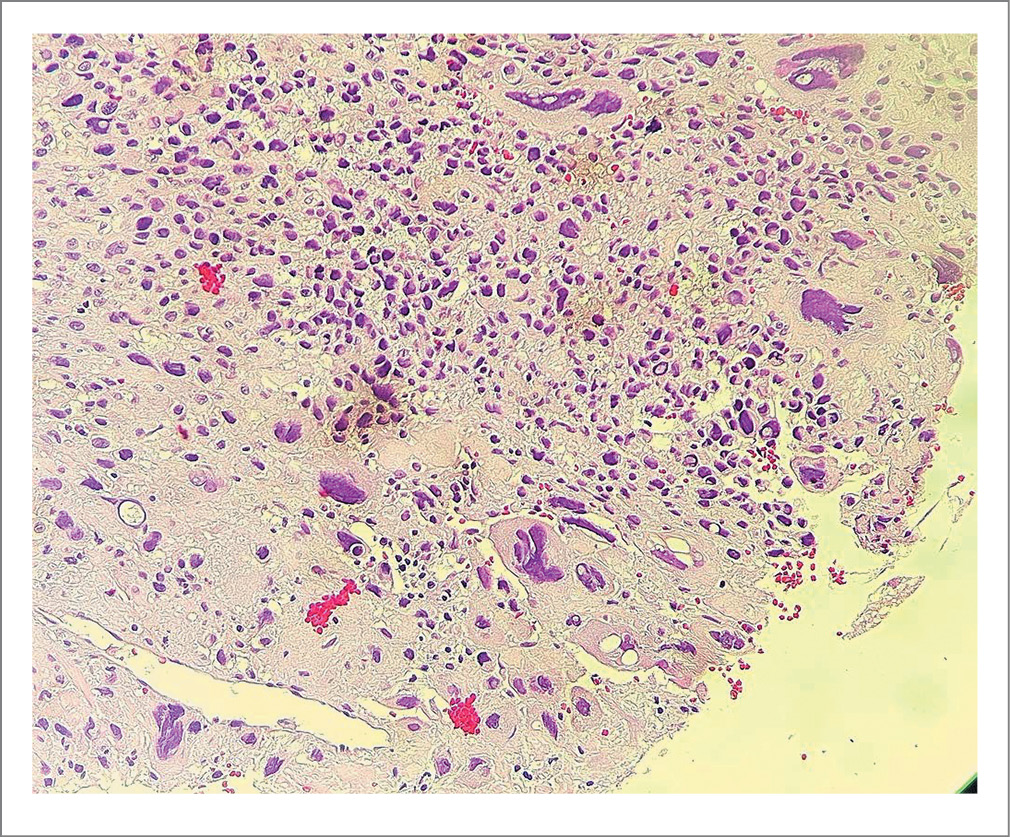

- Свертки крови, представленные частично лизированными и неизмененными эритроцитами, эндометрий без четких признаков стадии менструального цикла, с признаками очаговых гиперпластических изменений, без атипии. На этом фоне обнаружены крупные фрагменты эндометрия с ростом полиповидной опухолеподобной ткани, инфильтрирующей прилежащие части миометрия, построенной из крупных многогранных, преимущественно мононуклеарных, клеток, а также многочисленных сливающихся пластов клеток трофобласта с гигантскими гиперхромными ядрами с резко выраженным полиморфизмом. В пределах доставленного материала фокусов некрозов достоверно не обнаружено, признаков лимфоваскулярной инвазии также не выявлено (рис. 1, 2).

Рис. 2. Сливающиеся клетки трофобласта с формированием пластов, демонстрирующие выраженный ядерный полиморфизм. Окраска гематоксилин-эозином. ×20.

Fig. 2. Fused trophoblast cells with formation of layers, demonstrating pronounced nuclear polymorphism. Hematoxylin and eosin staining. ×20.